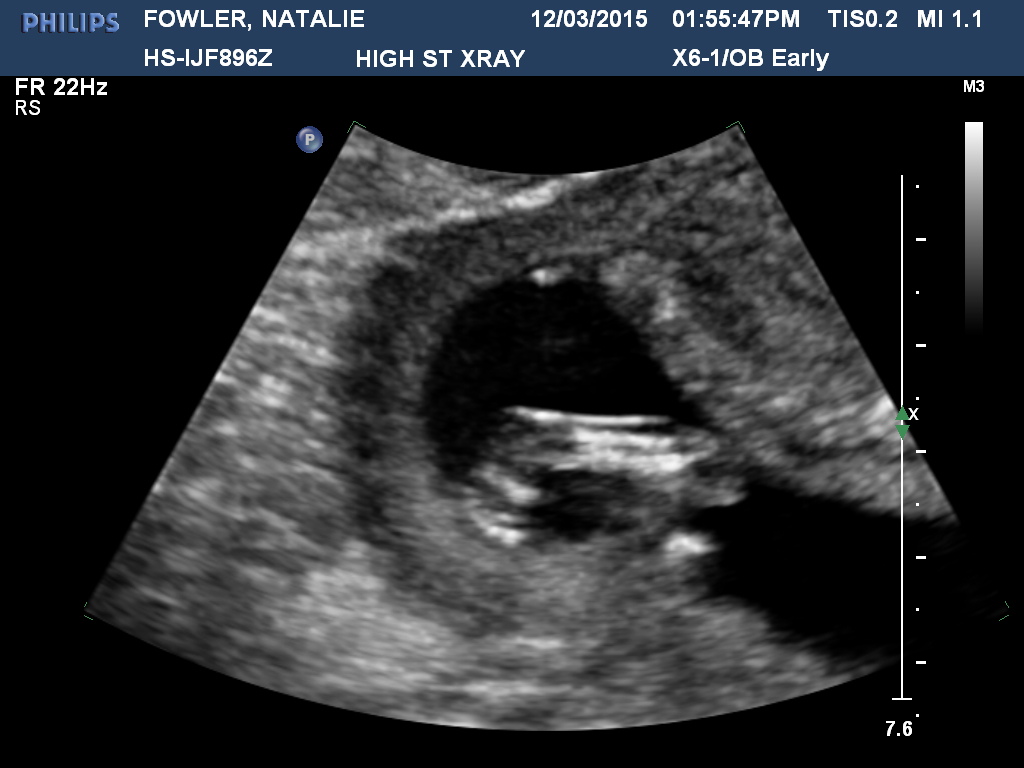

The longer I look at this scan, the more confused I get! Baby is measuring at 13w6d, any ideas would be amazing :)